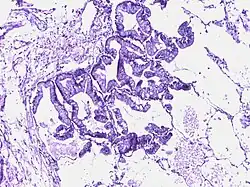

![]() |

Bronchoalveolar carcinoma | Lepidic pattern of growth of tumor cells along the alveolar wall resembling butterfly sitting on fence. Normal alveoli is seen towards right side. | Category: Histopathology of bronchio-alveolar carcinoma | Bronchio-alveolar carcinoma |